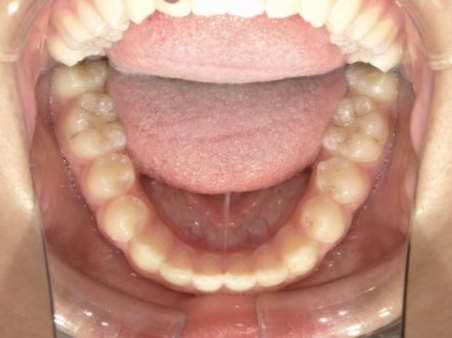

治療中⑨ 中3:14y4m

モノブロック装置で左上八重歯が改善しました

今後、必要によりマルチブラケット法へ移行予定です